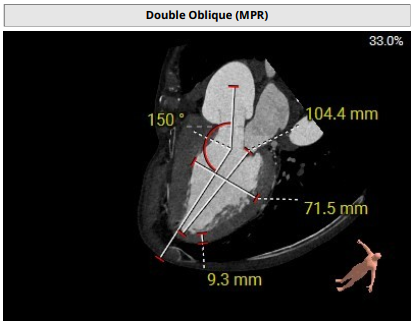

术前影像评估提示,患者主动脉瓣为三叶瓣,分布较均匀,无明显钙化。主动脉瓣环直径约25.5mm,左室流出道直径27.7mm,STJ直径49.9mm,升主动脉直径45.4 mm,冠脉开口高度充足(左冠12.4mm,右冠11.6mm),梗阻风险低。入路角度方面,左室-主动脉夹角为150°,心脏角度60°。

上下滑动查看更多照片